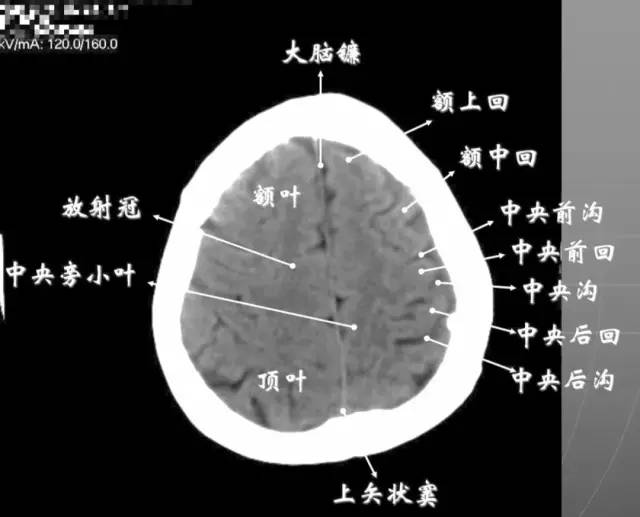

6、侧脑室上部层面内侧壁侧脑室体部被胼胝体分开,侧脑室体部的外方为顶叶,顶枕沟及中央沟将大脑为为额、顶、枕叶。

7、大脑皮质下部层面(半卵圆中心层面)在胼胝体和侧脑室上方,大脑镰自前向后贯穿中线。白质部分为半卵圆中心,额叶范围缩小,顶叶所占比例扩大,枕叶基本消失。

半卵圆中心:位于胼胝体上方,由左右大脑半球髓质形成的有髓纤维,对称位于大脑镰两侧区域。

8、大脑皮质上部层面(半卵圆区上部层面)已近颅顶,大脑镰清晰可见,其旁的脑灰质和脑沟十分清楚。顶叶较小,额叶较小。

放射冠:是内囊到大脑皮质间的放射状纤维白质。